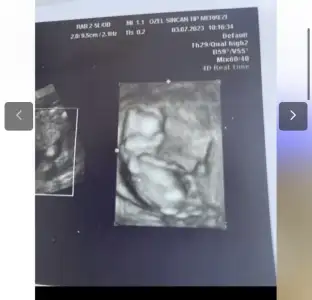

bana da tahmin yapar mısınız burda nub a göre kız demislerdi ilk usg fotoğrafı için 15. haftada doktor %60 erkek ama 1ay sonra bı daha bakalım dedi. 18inde detaylım var o zaman net belli olur ama sanki kız gibi geliyor bana karın şeklimden. ilk gebeligimde karnım alttan sivriydi oğlum var bunda karnım yuvarlar büyüyor bilemedim. çok göstermedi cinsiyet dr karnımı salladı falan 3-5dk ugrastı görmek icin %60 erkek ama belli değil diğer ay bakarız bıdaha dedi bilemedim valla siz ne diyorsunuzzKafa şekli burada erkek gibi. Nub çok düz değil ama çok dikte değil. Pozisyondan kaynaklanıyor sanırım. Şimdilik erkek diyebilirim. Benim bebeğimle böyle kendini tam belli etmedi sonra bir prenses olduğu belli oldu. Rabbim gönlündekini nasip etsin inşallah hayırlısı ve sağlıkla.

Evet kız gibi duruyor ay sağlıkla gelsin inşallah gönlünüzden geçen olurbana da tahmin yapar mısınız burda nub a göre kız demislerdi ilk usg fotoğrafı için 15. haftada doktor %60 erkek ama 1ay sonra bı daha bakalım dedi. 18inde detaylım var o zaman net belli olur ama sanki kız gibi geliyor bana karın şeklimden. ilk gebeligimde karnım alttan sivriydi oğlum var bunda karnım yuvarlar büyüyor bilemedim. çok göstermedi cinsiyet dr karnımı salladı falan 3-5dk ugrastı görmek icin %60 erkek ama belli değil diğer ay bakarız bıdaha dedi bilemedim valla siz ne diyorsunuzz